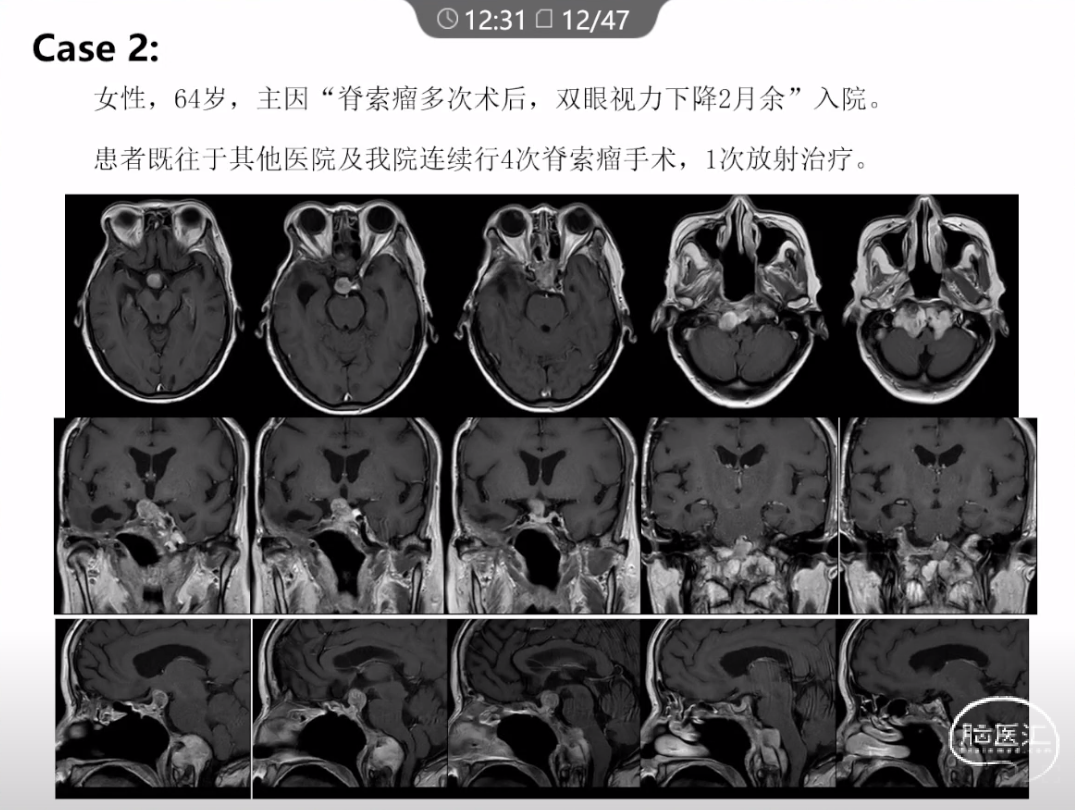

本文主要内容为:脊索瘤临床特点、治疗选择,以及多个手术病例。